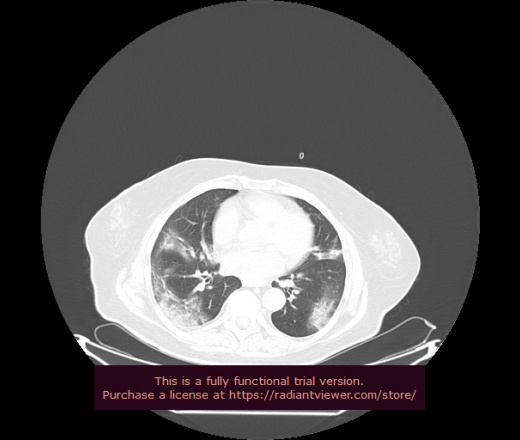

Уважаемые коллеги, если имеется интерес, сможете ли Вы спрогнозировать дальнейшее +-одинаковое течение процесса у 4 данных разных пациентов? Зацепиться где-то можно очень просто, где-то нельзя.

2 ID:88436